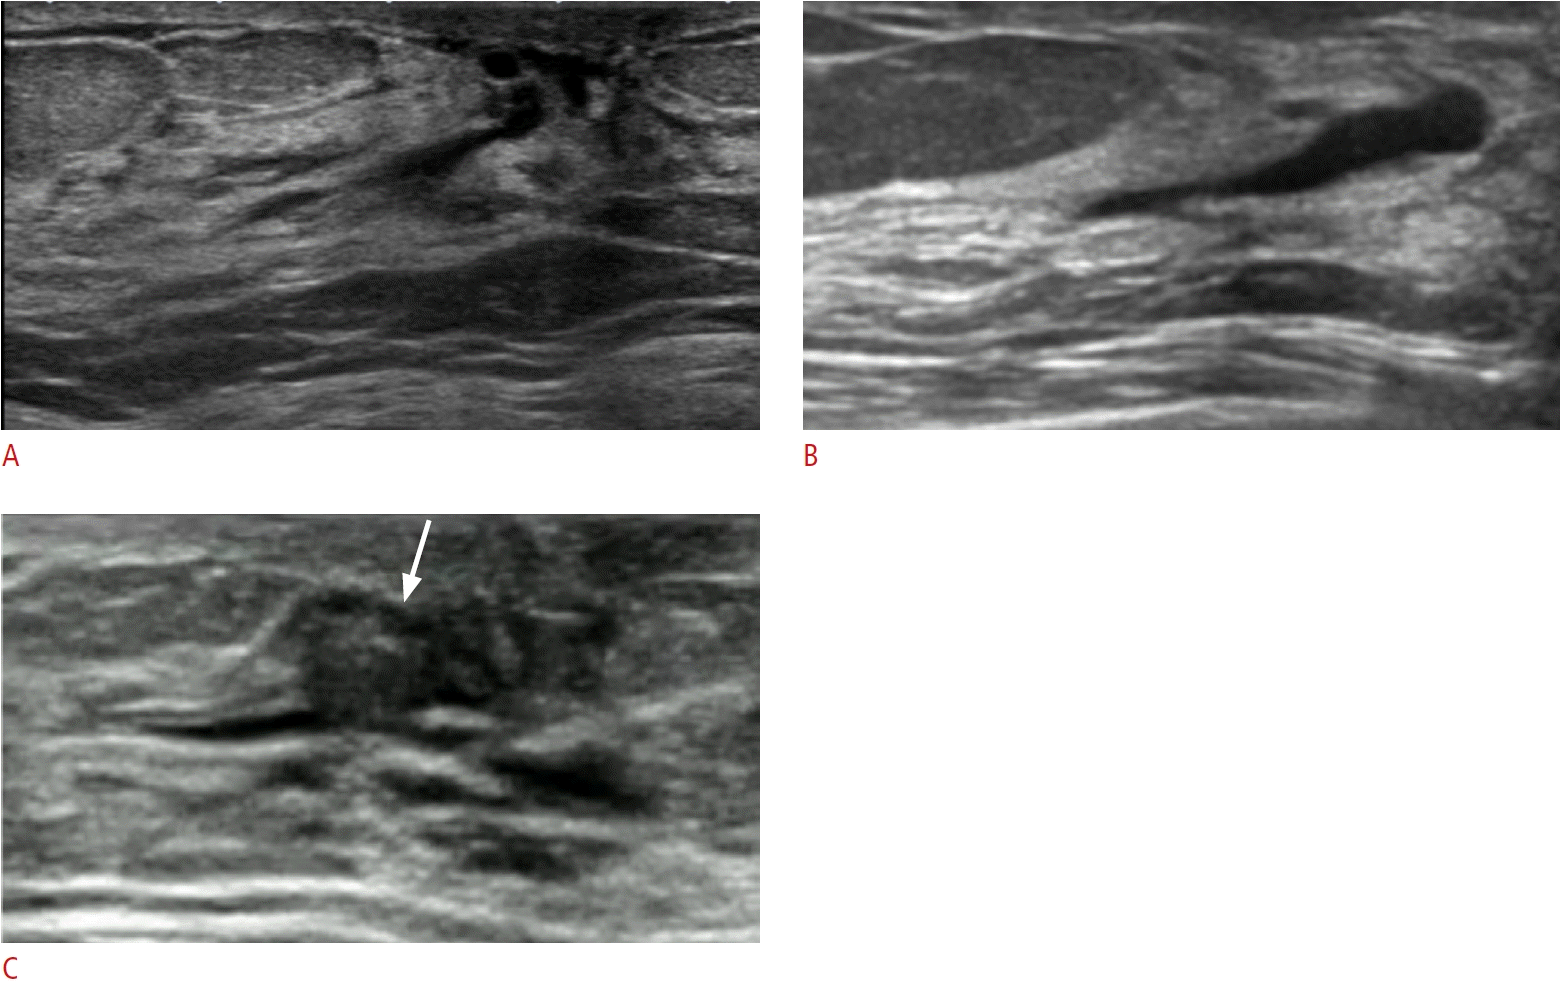

33. Stavros AT. Nontargeted indications: breast secretions, nipple discharge, and intraductal papillary lesions of the breast. In: Stavros AT, ed. Breast ultrasound. Philadelphia, PA: Lippincott Williams & Wilkins, 2004;157-198.

13. Ferris-James DM, Iuanow E, Mehta TS, Shaheen RM, Slanetz PJ. Imaging approaches to diagnosis and management of common ductal abnormalities. Radiographics. 2012; 32:1009–1030.

17. Ban K, Tsunoda H, Watanabe T, Kaoku S, Yamaguchi T, Ueno E, et al. Characteristics of ultrasonographic images of ductal carcinoma in situ with abnormalities of the ducts. J Med Ultrason (2001). 2020; 147:107–115.